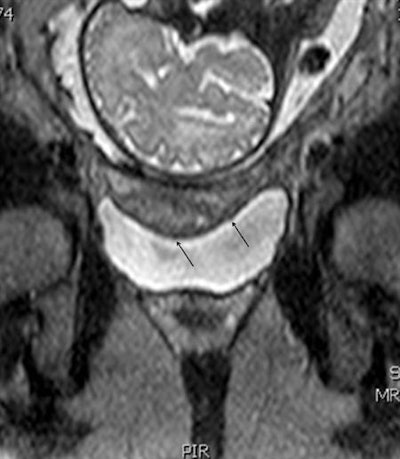

MRI (coronal survey image) of the placenta in a 31-week gestational age twin pregnancy shows kissing placentae. All images courtesy of Dr. Papaioannou Georgia, Panagiotis Tagalakis, and Dr. Christina Malamateniou.The group performed a total of 26 placental MRI examinations, with the indications as follows: